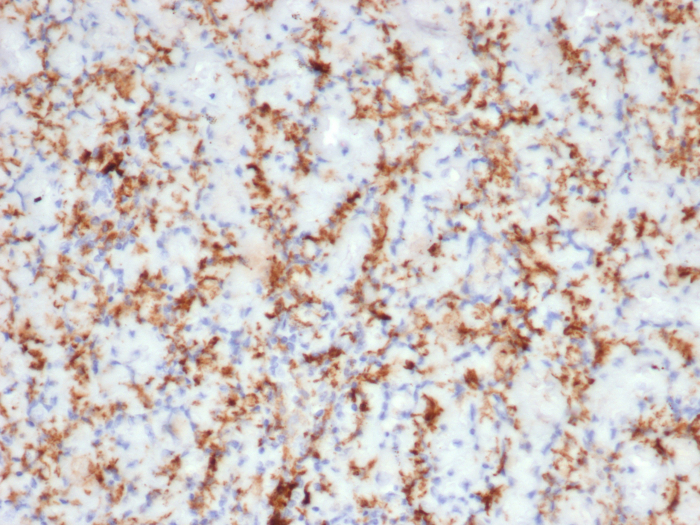

Formalin-fixed, paraffin-embedded human tonsil stained with CD163 antibody (M130/3708R). HIER: Tris/EDTA, pH9.0, 45min. Secondary: HRP-polymer, 30min. DAB, 5min.